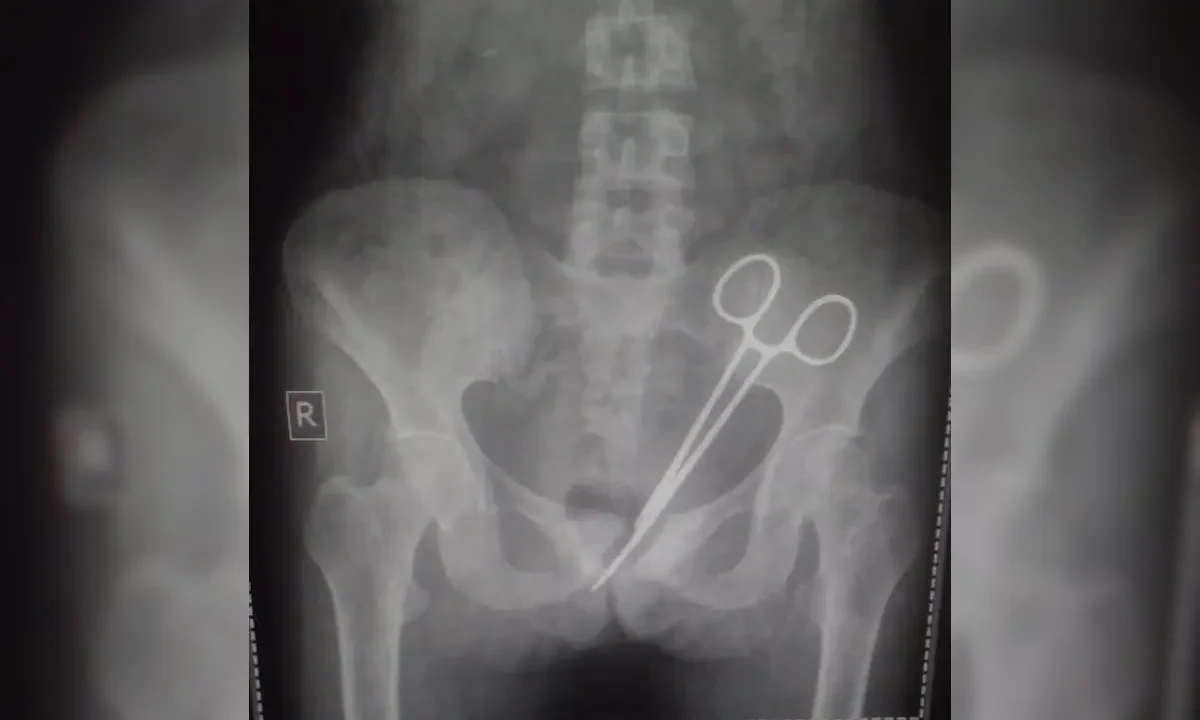

The disciplinary action comes after a preliminary investigation confirmed a harrowing instance of medical negligence: a pair of surgical scissors was allegedly left inside the patient’s body during a procedure at the Abubakar Imam Urology Centre.

The tragedy has cast a somber shadow over the state’s medical community, raising urgent questions about theatre protocols and the safety of surgical patients. Following the outcry surrounding the death of Ms. Umar, the Executive Secretary of the Board, Dr. Mansur Mudi Nagoda, ordered an immediate internal probe to verify the claims. The results of that investigation, released this weekend, confirmed that the lapse in professional standards did indeed occur within the walls of the specialized facility.

However, the incident has touched a nerve with the public. Many are asking how a basic “instrument count”, a standard global practice where every tool is accounted for before a patient is stitched up, could have failed so spectacularly. In medical circles, leaving a foreign object inside a patient is often referred to as a “never event”, an error so egregious that it should never occur if basic safety checklists are followed.